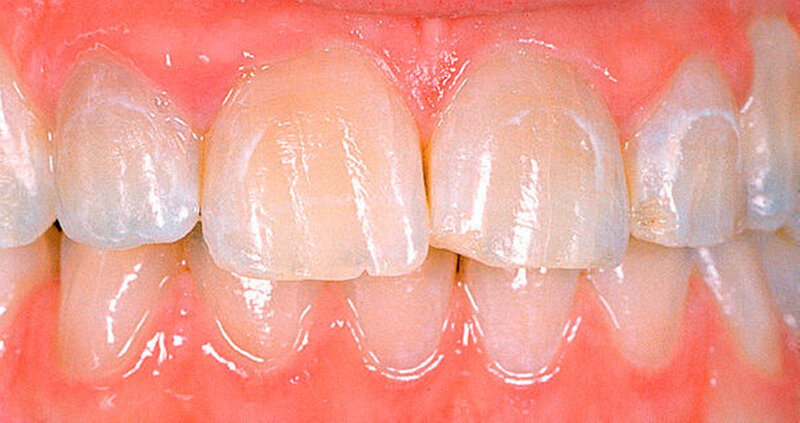

Bei dieser genetisch bedingten Schmelzdysplasie sind in der Regel alle Zähne einer oder beider Dentitionen betroffen, und es ist ein bilateralsymmetrisches Erscheinungsbild vorhanden. Die Ausprägung der Schmelzdefekte kann von Zahn zu Zahn und von Generation zu Generation variieren (Abbildungen 1a bis 1c). Die Struktur des Dentins ist nicht verändert. Die Schmelzdefekte treten als Grübchen von unterschiedlicher Größe in mehr oder weniger normal dickem Schmelz in Erscheinung (Abbildung 2a). Durch Einlagerung von Farbstoffen in diese Grübchen können die Schmelzveränderungen ästhetisch störend wirken (Abbildung 2b). Ähnliche grübchenartige Schmelzhypoplasien können bei Patienten mit Rachitis, Pseudohypoparathyroidismus oder Epidermolysis bullosa beobachtet werden. Bei der hypoplastischen Form der Amelogenesis imperfecta ist die Schmelzhärte normal, die Schmelzdicke jedoch reduziert. Der grübchenartige Typ weist als Ausnahme eine fast normale Schmelzdicke auf (Abbildungen 3 und 4).

Je nach Typ kann der Schmelz an bestimmten Zahnstellen völlig fehlen. Deshalb kann die Zahnform bereits beim Zahndurchbruch stark verändert sein.

Die Amelogenesis imperfecta kann neben der hypoplastischen Form in eine hypomaturierte Form und eine hypokalzifizierte Form eingeteilt werden. Auch Kombinationen der verschiedenen Formen der Amelogenesis imperfecta wurden beschrieben. Bei der hypomaturierten Form ist die Schmelzhärte weicher als normal, die Schmelzdicke entspricht beim Durchbruch der Zähne der Norm. Bei der hypokalzifizierten Form ist der Schmelz sehr weich und die Schmelzdicke beim Zahndurchbruch normal. Deshalb sind vor allem bei der hypomaturierten und hypokalzifizierten Form die Abrasion und Attrition stark erhöht. Bei beiden Formen ist die Zahnfarbe beim Durchbruch der Zähne opakweiß bis gelblich. Mit zunehmendem Alter werden die Zähne braun. Die Prävalenz der Amelogenesis imperfecta beträgt je nach Population und Typ zwischen 1: 700 bis 1 : 20.000.